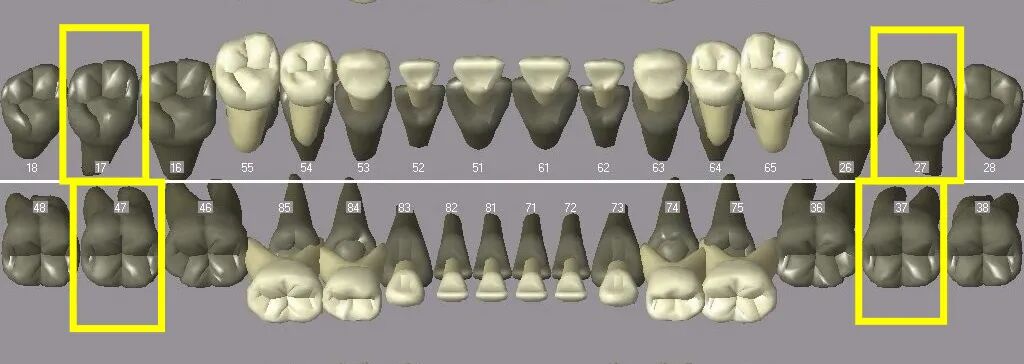

换牙这场“马拉松”,总体分为三程:

1. 第一程:从5-7岁开始,持续2-3年

曲面断层片怎么看换牙与身高有关吗?关于孩子换牙的所有疑问一篇说清_https://www.jmylbn.com_新闻资讯_第4张

曲面断层片怎么看换牙与身高有关吗?关于孩子换牙的所有疑问一篇说清_https://www.jmylbn.com_新闻资讯_第5张

图注:8颗乳前牙脱落,8颗对应的恒前牙萌出;4颗第一恒磨牙(六龄齿)直接萌出。

2. 第二程:从8-10岁开始,持续2-3年

曲面断层片怎么看换牙与身高有关吗?关于孩子换牙的所有疑问一篇说清_https://www.jmylbn.com_新闻资讯_第6张

曲面断层片怎么看换牙与身高有关吗?关于孩子换牙的所有疑问一篇说清_https://www.jmylbn.com_新闻资讯_第7张

图注:8颗乳磨牙+4颗乳尖牙脱落,8颗对应的前磨牙+4颗对应的恒尖牙萌出。

3. 第三程:一般10-12岁

曲面断层片怎么看换牙与身高有关吗?关于孩子换牙的所有疑问一篇说清_https://www.jmylbn.com_新闻资讯_第8张

曲面断层片怎么看换牙与身高有关吗?关于孩子换牙的所有疑问一篇说清_https://www.jmylbn.com_新闻资讯_第9张

图注:4颗第二恒磨牙直接萌出